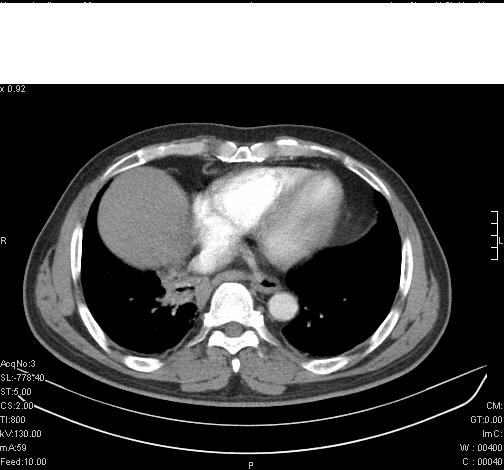

标题: CT6685:右肺阻塞性炎症,增强CT。 [打印本页]

标题: CT6685:右肺阻塞性炎症,增强CT。

前几天,发了患者的平扫片,患者抗炎一周后增强扫描。右中叶病灶吸收明显,但下叶病灶未见明显吸收。右肺门可见结节影,看来凶多吉少

右肺下叶支气管管腔狭窄,管壁增厚,右下肺见斑片状高密度影,考虑右侧肺门中心肺癌伴阻塞性肺炎

右肺下叶支气管壁明显增厚,考虑癌症并阻塞性炎症、肺门淋巴结肿大

考虑右肺癌并阻塞性炎症、肺门淋巴结肿大

右肺下叶支气管壁不规则增厚,右肺下叶有斑片状影分布。考虑右肺中央型肺癌伴右肺下叶阻塞性改变。建议支纤镜检查。平扫比增强较好显示了病变情况。

右主支气管狭窄,管壁增厚。考虑右中心性肺ca伴阻塞性肺炎。

既然抗炎治疗有效,可继续治疗;右肺下叶支气管管腔狭窄,管壁增厚,右下肺见斑片状高密度影,右侧主支气管后见结节影(淋巴结?),肺癌不能排出。